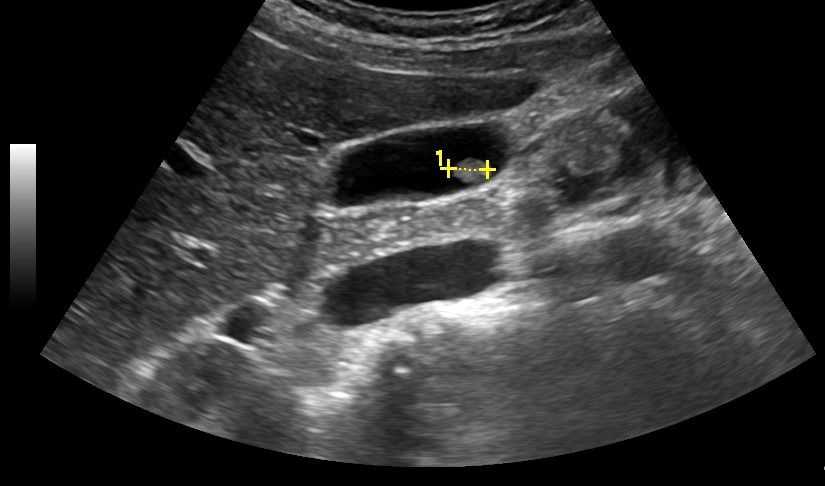

Η ανίχνευση λιθίασης σε ασθενείς με συμπτώματα (κοιλιακό άλγος, κωλικό) επιτρέπει την αξιολόγηση της βαρύτητας της νόσου:

- Σε περίπτωση νεφρολιθίασης: βαθμός διάτασης του πυελοκαλυκικού (αποχετευτικού) συστήματος του νεφρού, διερεύνηση της εντόπισης του λίθου (στο νεφρό, τον ουρητήρα ή την ουροδόχο κύστη)